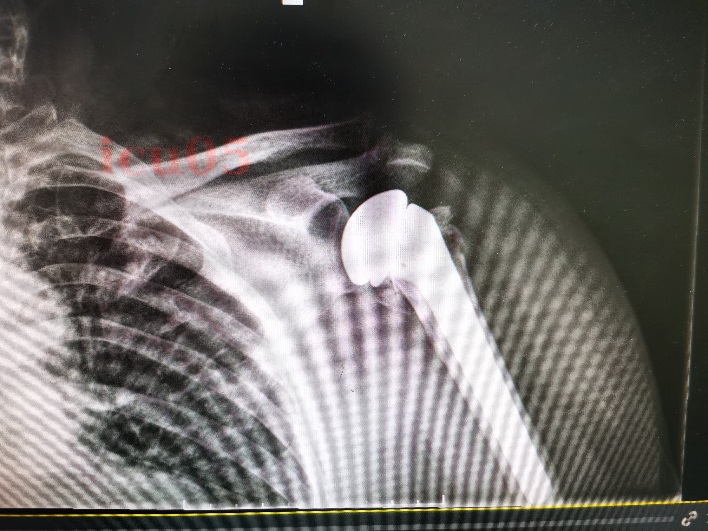

术后X光片示人工假体位置满意